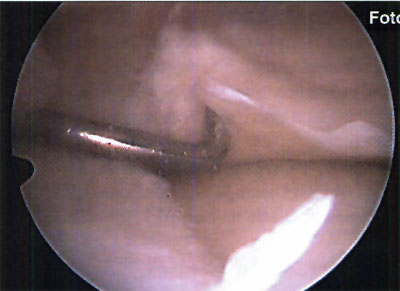

En relación al tratamiento quirúrgico, se realizó debridamiento de la lesión en 6 (26,1%) pacientes, debridamiento y perforaciones en 12 pacientes (52,2%) y en 5 pacientes se efectuó injerto osteocondral (21,7%). (fotos 11 y 12 )

Foto 11: Debridamiento y Perforaciones

Foto 12: cuerpo libre intraarticular